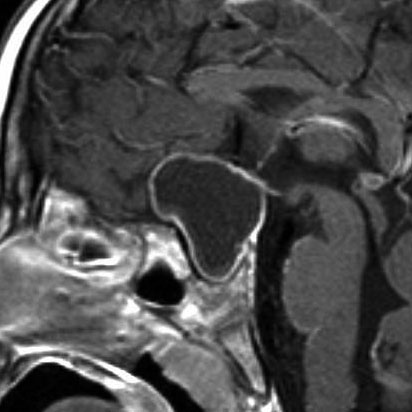

7歳の子が視力障害で発症しました。両耳側半盲という症状です。典型的な鞍隔膜下頭蓋咽頭腫です。ガドリニウム造影剤を入れないMRIでみえる,黄色い矢印の先の白い高信号は抗利尿ホルモンです。ですから下垂体機能もまだ残っていて,尿崩症はありません。視力障害が戻らないことがあるのでなるべく早く,経鼻的な手術で摘出した方がいいものです,簡単 o(^-^)o